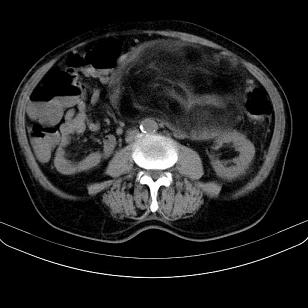

标题: CT21671:男,88岁,左上腹包块 [打印本页]

标题: CT21671:男,88岁,左上腹包块

患者因咳嗽而住院,自觉右上腹包块,无其他不适。

腹膜后高分化脂肪肉瘤

腹膜后脂肪肉瘤

腹膜生占位性病变,脂肪肉瘤可能。

脂肪肉瘤,应测ct值。

左侧腹膜后脂肪肉瘤。